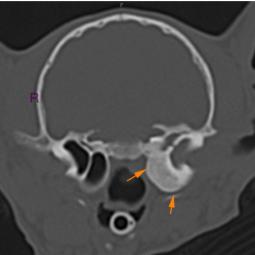

La trépanation de la bulle tympanique:

Cette technique chirurgicale consiste à perforer la paroi de la bulle tympanique et nettoyer son contenu. La chirurgie est nécessaire lors d'otite moyenne (accumulation de liquide dans la bulle tympanique) qui ne régresse pas avec un traitement médical.

Le diagnostic peut se faire par radiographie (cf images joints) mais l'examen de choix reste le scanner ou l'IRM si on souhaite une exploration fine de l'oreille interne.

A noter que les images présentes ici sont celles d'un chaton qui présente une otite moyenne droite modérée qui a été soignée à l'aide d'un traitement anti-inflammatoire et antibiotique.

Polype naso-pharyngien visualisé au scanner

Même polype mais étendu à l'oreille moyenne droite